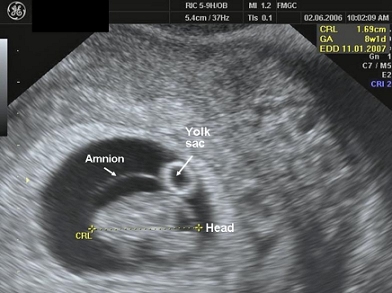

Gebelik kesesi (gestasyonel sac) artık transvaginal ultrasonla 5.haftada mutlaka rahim içinde görülmelidir.Yaklaşık 1 cm büyüklüğe ulaşır. Bu esnada kanda gebelik testi B-HCG 1500-2400 civarındadır. Gebelik kesesi kalınlaşmış rahim iç duvarı içinde yaklaşık 8-10 mm boyutunda koyu renkli bir halka şeklinde görülür ve günde 1-2 mm büyür. Gebelik kesesi yaklaşık 1 cm büyüklüğe ulaştığında yolc sac da görünmeye başlar. Ortalama 1.5 cm çaplı gebelik kese içinde embrio ve yolc sac birlikte görülür.

Bu esnada embrio gebelik kesesi içerisinde hızla gelişmektedir. Yaklaşık 2-5 mm boyutundadır ve 3-4 mm büyüklüğünde yuvarlak beyaz halka şeklinde izlenen yolc kesesine yakın yerleşimlidir.

7. haftada embriyonun baş-popo mesafesi (CRL) 6 mm den 11 mm’ye büyür. Gelişmenin bu fazında beyin hızlı geliştiğinden baş vucudun diğer kısımlarına göre daha büyük görülür.

Gebeliğinizin sağlıklı gidişatı açısından embrio uzunluğunun amniotik kese büyüklüğüne oranı önemli bir parametredir. Normal erken gebeliklerde amniotik kese-embrio uzunluğu 5mm’den büyük olmalıdır. Yolc kesesi de normal gebeliklerde tipik olarak 6 mm’nin altında olmalıdır.